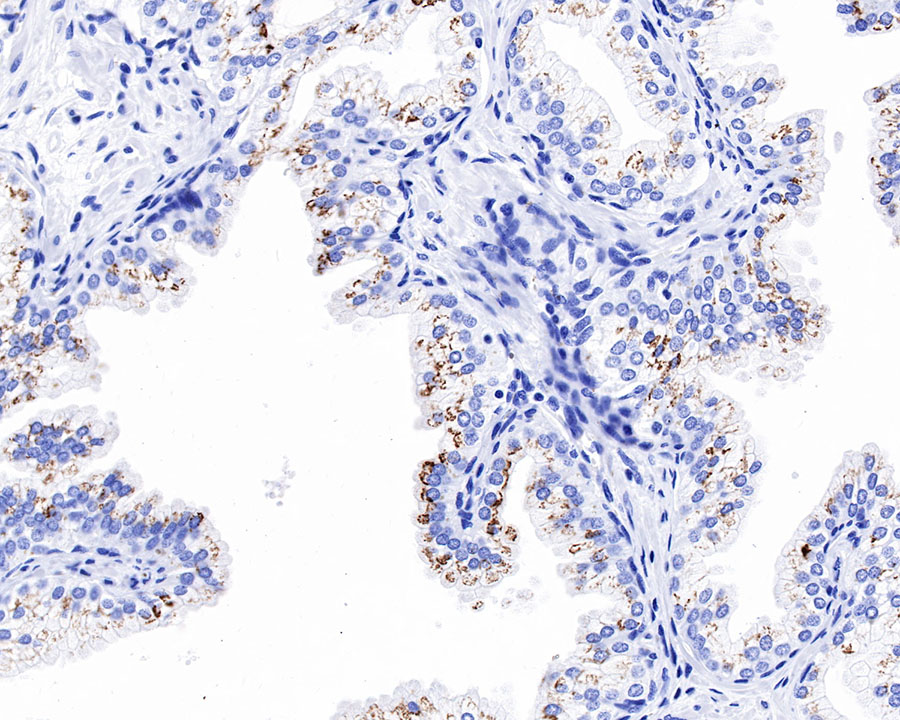

IHC shows positive staining in paraffin-embedded human prostate. Anti-GP73/GOLPH2 antibody was used at 1/1000 dilution, followed by a HRP Polymer for Mouse & Rabbit IgG (ready to use). Counterstained with hematoxylin. Heat mediated antigen retrieval with Tris/EDTA buffer pH9.0 was performed before commencing with IHC staining protocol.